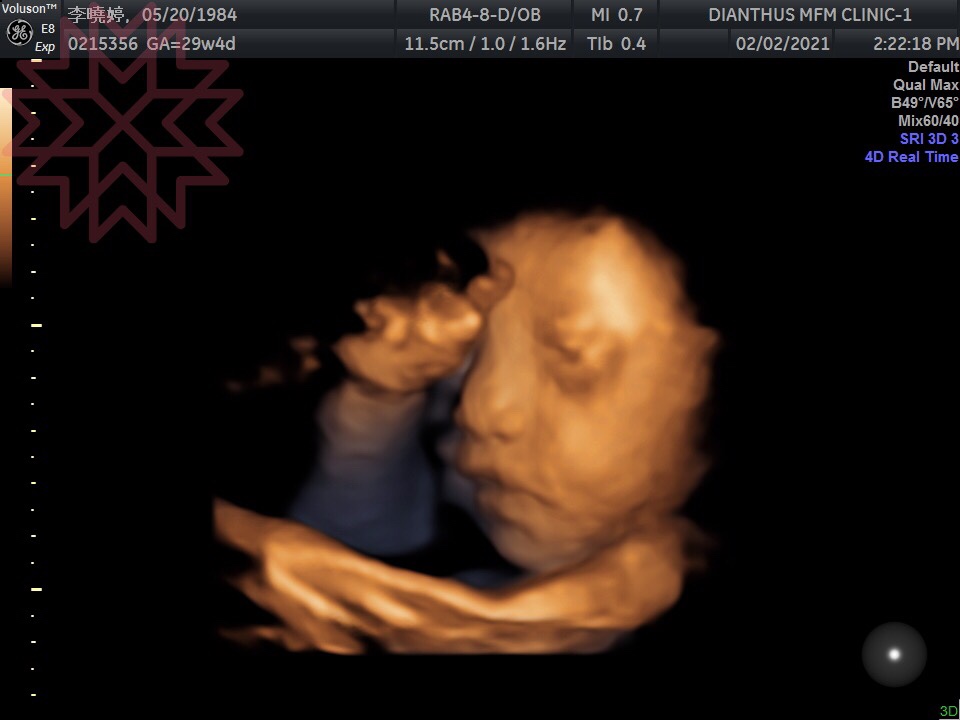

下半年來了個驚喜,原本是想,疫情走完上半年,最壞、最不確定的狀況已過,下半年會否極泰來,生活工作恢復往常,沒想到懷了疫情寶寶,預產期110年4月。心中當然是開心的,但在初期整整4個月不想動,曾經還有幾次早會時,跑到廁所一關上門,就像噴泉式的吐了整個馬桶,之後很悲情的用衛生紙把週圍清乾淨。仔細看了那四個月的行事曆,幾乎沒做什麼事……坦白說,可以理解當時的狀態,為什麼4個月什麼事都不想做,在2年前有胚胎萎縮過,有點害怕生命殘忍的淘汰機制,不知道這一次是否能夠順利過每個關卡。當我們不斷地從螢幕看到藍天充滿生命力的四肢、 聽到他強而有力的心跳時,既覺得不可思議,又緩慢地認知到自己真的懷孕的事實。

8個月29週藍天,希望有爸爸性感的嘴唇!